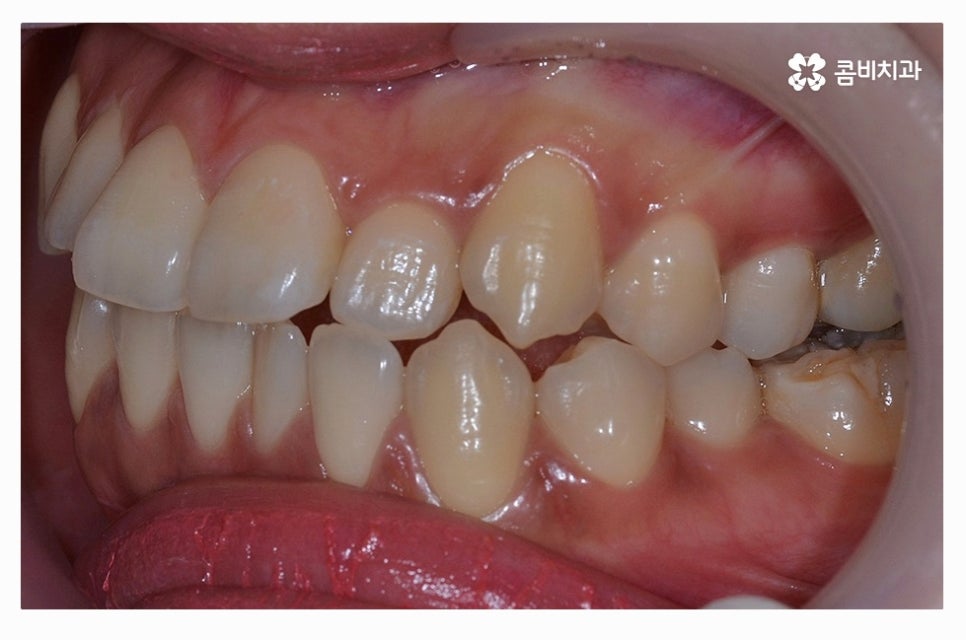

따라서 덧니교정에 있어서 정밀검진과 구강 상태를 면밀하게

살펴보고 전문의와 충분한 상담을 하는 것이 우선이며

덧니교정을 하는 분들 중에서 치열뿐 아니라 돌출입으로

고민하는 분들도 많기 때문에 치아의 이동 공간을

확보하고 치아가 이동한 후에 얼굴 변화까지 고려하실 필요가 있어요.